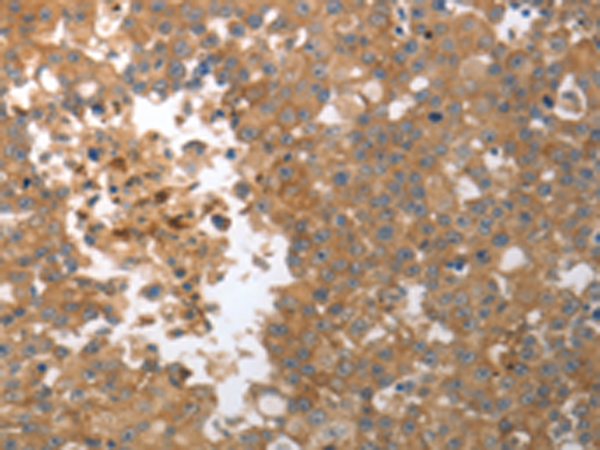

分类: 科研抗体货号: P11039别名: MMP-27应用: IHC反应种属: Human